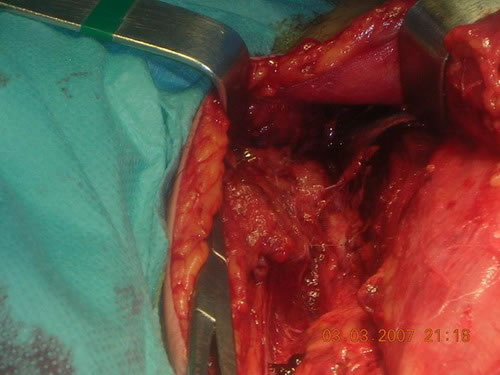

En la intervención se encuentran desgarros y detritus musculo aponeuróticos en dos trayectorias de las longitudes citadas anteriormente y donde se encuentra partcipación de todos los planos del muslo anterior hasta el suelo de la cadera con afectación del triángulo de Scarpa, disección del paquete femoral y arrancamiento de la vena safena interna a 10 cm. de su cayado en la vena femoral.

Se realiza el procedimiento quirúrgico habitual de limpieza de detritus, lavado de las heridas, reparación de las fascias musculares, reparación de los planos musculares afectados, extirpación de la Safena restante y colocación de drenajes (2) uno en el plano superficial y otro mayor en el profundo.

Detalles gráficos